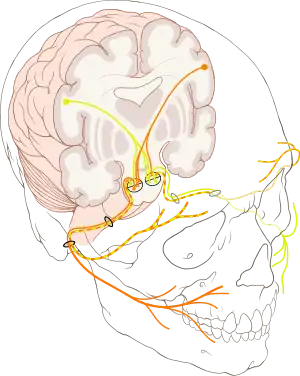

The cause of Bell's palsy is unknown[1] and it can occur at any age.[4] Risk factors include diabetes, a recent upper respiratory tract infection, and pregnancy.[1][7] It results from a dysfunction of cranial nerve VII (the facial nerve).[1] Many believe that this is due to a viral infection that results in swelling.[1] Diagnosis is based on a person's appearance and ruling out other possible causes.[1] Other conditions that can cause facial weakness include brain tumor, stroke, Ramsay Hunt syndrome type 2, myasthenia gravis, and Lyme disease.[2]

The facial nerve controls a number of functions, such as blinking and closing the eyes, smiling, frowning, lacrimation, salivation, flaring nostrils and raising eyebrows. It also carries taste sensations from the anterior two-thirds of the tongue, through the chorda tympani nerve (a branch of the facial nerve). Because of this, people with Bell's palsy may present with loss of taste sensation in the anterior 2⁄3 of the tongue on the affected side.[15]

Bell's palsy is the result of a malfunction of the facial nerve (cranial nerve VII), which controls the muscles of the face. Facial palsy is typified by inability to move the muscles of facial expression. The paralysis is of the infranuclear/lower motor neuron type.

It is thought that as a result of inflammation of the facial nerve, pressure is produced on the nerve where it exits the skull within its bony canal (the stylomastoid foramen), blocking the transmission of neural signals or damaging the nerve. Patients with facial palsy for which an underlying cause can be found are not considered to have Bell's palsy per se. Possible causes of facial paralysis include tumor, meningitis, stroke, diabetes mellitus, head trauma and inflammatory diseases of the cranial nerves (sarcoidosis, brucellosis, etc.). In these conditions, the neurologic findings are rarely restricted to the facial nerve. Babies can be born with facial palsy.[25] In a few cases, bilateral facial palsy has been associated with acute HIV infection.